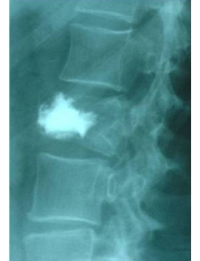

Pre- and post-operative comparison of a cemented kyphoplasty

Female, age 55, compression fracture of L2

After 1

after 2